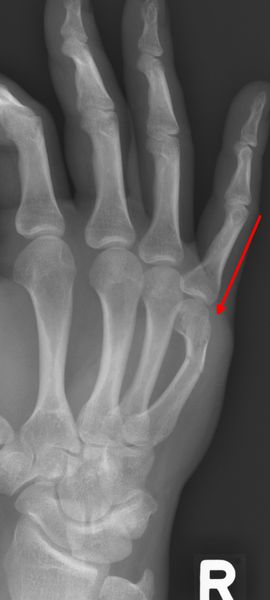

Rolandofraktur: basisnahe y- oder T-förmiger Bruch mit Gelenkbeteiligung.